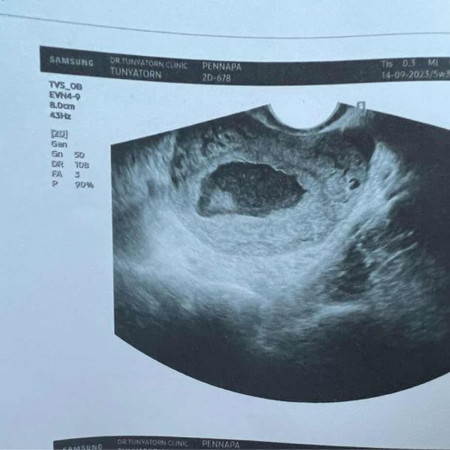

ถุงตั้งครรภ์ไม่สวยมีโอกาสได้ไปต่อไหมคะ ตอนนี้เครียดมากเลยค่ะ คุณหมอบอกอาจจะหลุด ตอนนี้5สัปดาห์แล้วค่ะ